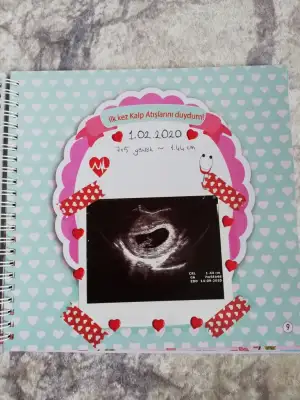

Senın kıtaplar konusundakı bılgıne guvenıyorum aldım kuzum ama sadece dogal dogum stokta vardı dıgerlerı yoktu,sen okudukca bana onerırsen cok mutlu olurumdediğin gibi hepsi çok detaya boğulmuş kuzum, benim bi tane mor kapaklı çok sevdiğim defterim vardı ben oraya yazıyorum her ultrasonda görmeye gittiğimizde, neleri aşerdiğimi, kalp atışını duyduğumuzda neler hissetiğimizi vs. ultrason fotilerini de oraya yapıştırıyorum

Eki Görüntüle 2589843

Eki Görüntüle 2589844

Eki Görüntüle 2589845

Eki Görüntüle 2589846